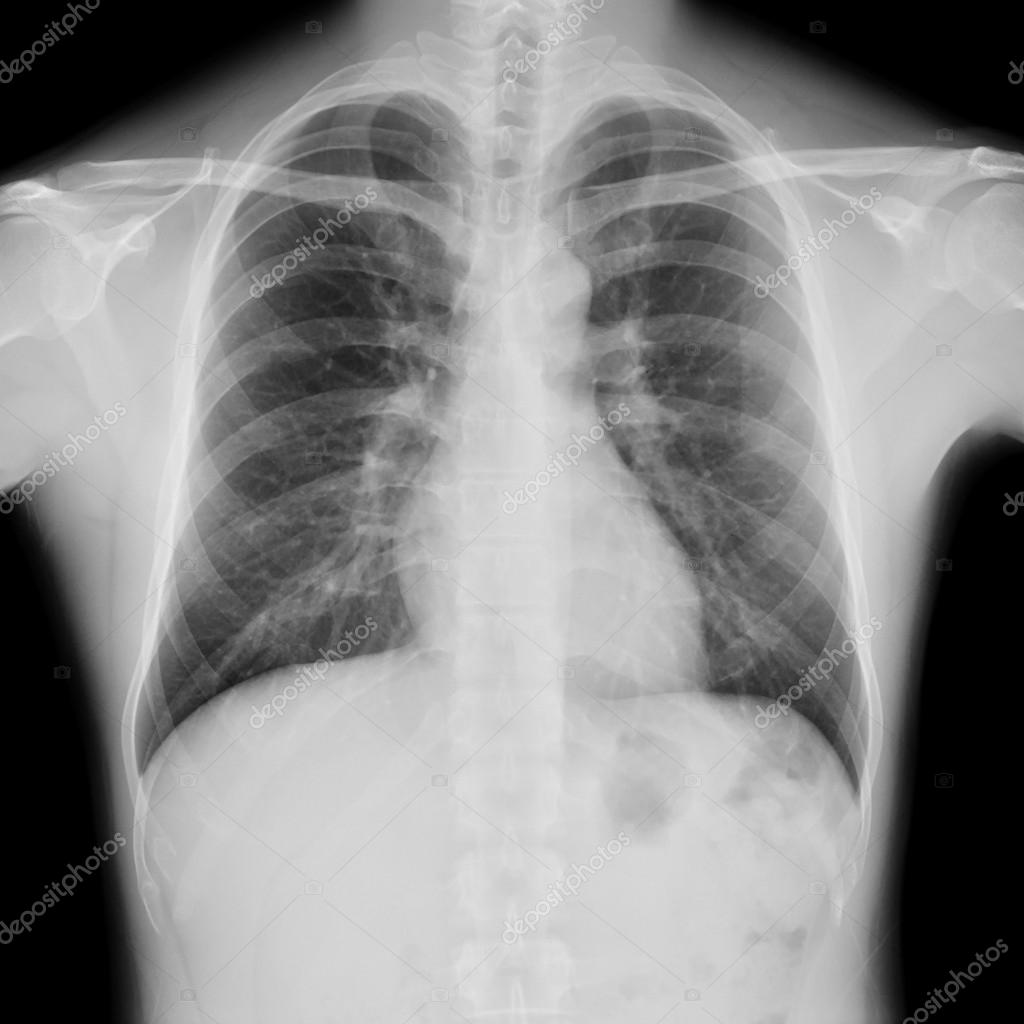

Normal Chest X Ray Man . — this chapter describes the normal anatomy of the airways, lungs, mediastinum, and diaphragm, as demonstrated on chest radiography (fig. In fact every radiologst should be an. Click now to learn the steps and helpful mnemonics at kenhub! There is a degree of hyperinflation as evidenced by both increased. Reading like the pros | radiology key. There are no visible nodules, tumors or masses. — this article lists examples of normal imaging of the chest and surrounding structures, divided by modality.

Normal Chest X Ray Man There is a degree of hyperinflation as evidenced by both increased. — this article lists examples of normal imaging of the chest and surrounding structures, divided by modality. Reading like the pros | radiology key. Click now to learn the steps and helpful mnemonics at kenhub! There are no visible nodules, tumors or masses. There is a degree of hyperinflation as evidenced by both increased. In fact every radiologst should be an. — this chapter describes the normal anatomy of the airways, lungs, mediastinum, and diaphragm, as demonstrated on chest radiography (fig.